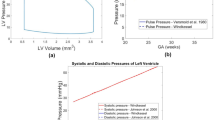

Image-based, patient-specific FE modeling of fetal LV myocardial biomechanics was performed in accordance with our previous methodologies (Green et al. 2022; Ong et al. 2020), where the FE model was connected to a lumped parameter model to enable ventricular-vascular coupling (Pennati et al. 1997; Pennati and Fumero 2000). The lumped parameter model used was based on Pennati et al.’s work (Pennati et al. 1997; Pennati and Fumero 2000) and was age scalable to a range of gestational ages, through a series of allometric equations. The model underwent minor recalibration using descending aorta pulse pressure measurements (Versmold et al. 1981) and more recent measurements of human fetal intracardiac pressure (Johnson et al. 2000), further details have been supplied in Supplementary Material Section 3.0. Our FE and lumped parameter codes have been made available at https://github.com/WeiXuanChan/heartFEM.

Further analysis of vFAV biomechanics outputs was conducted and compared with the parameter values for the healthy fetal hearts, which have been indicated by the horizontal blue dotted line in Fig. 4. These age-dependent healthy parameters were obtained from Parasuraman et al. for AV velocity measurements ranging from 12 to 40 weeks gestation (n = 221) (Parasuraman et al. 2013), from Johnson et al. for intracardiac pressure measurements during peak systole and end diastole, across 16–29 weeks gestation (n = 39) (Johnson et al. 2000), where the peak systolic pressure trendline was extended to 30 + 2 wks + days gestation and the diastolic LV pressures were assumed to indicate peak LA pressures, and from Devore et al. for stroke volume measurements, ranging from 20 to 40 weeks gestation (n = 200) (Devore et al. 2019). Healthy fetal heart myofiber stresses had not been reported in the literature. We therefore estimated healthy fetal LV myofiber stress via image-based simulations of 6 healthy fetal hearts, as explained in Supplementary Material Section 6.0, where we found that myofiber stresses were 12.19 ± 2.62 kPa and appeared to be invariant with age (Supplementary Fig. S5).